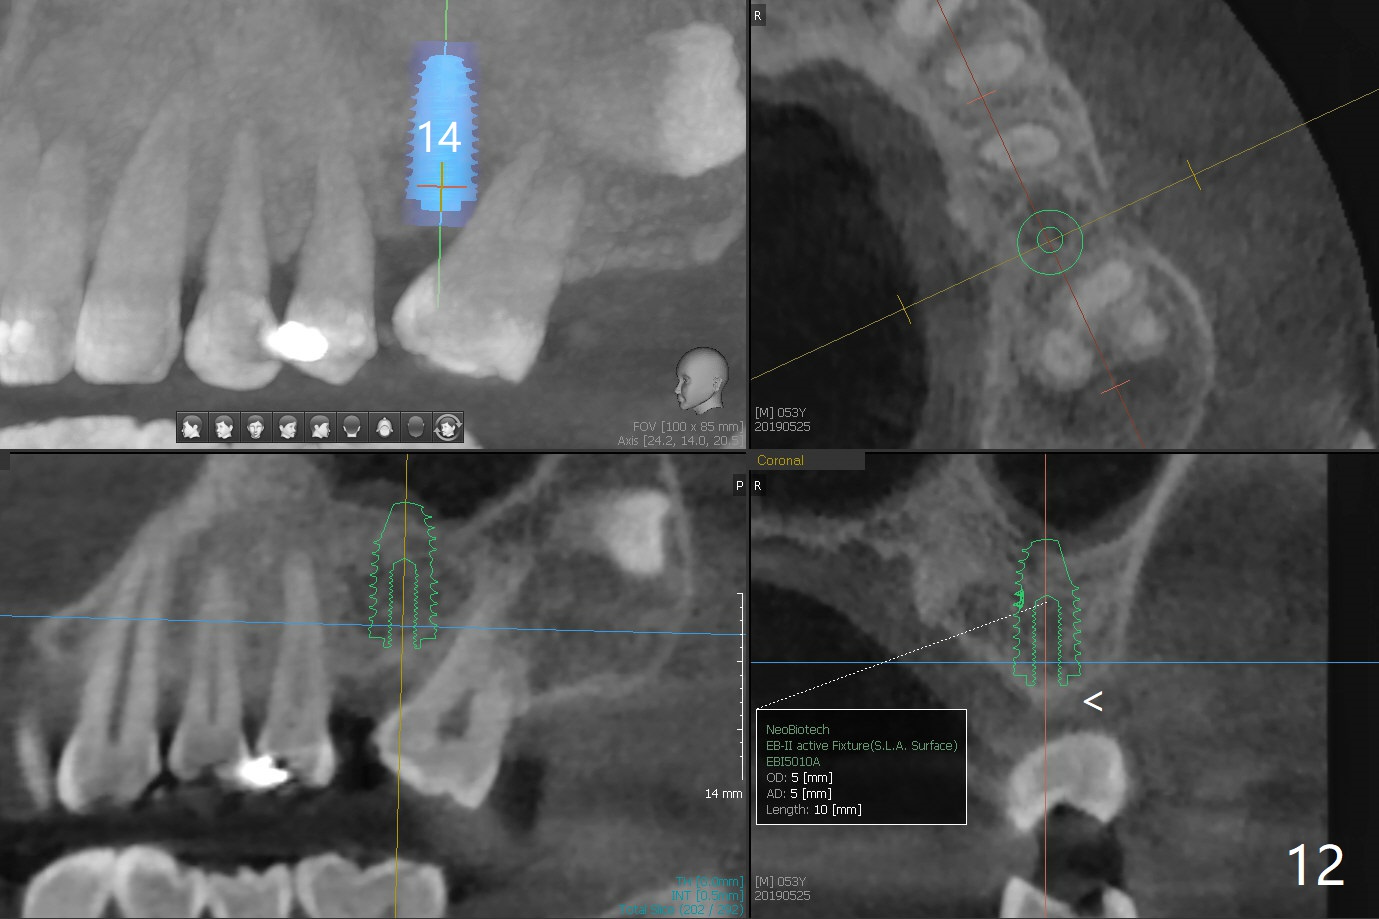

Crown/Implant Ratio

A 53-year-old man has signs of bruxism (Fig.1 diastema *) and root fracture or RCT failure at #4 (Fig.4 (large PARL *)). The RCT failure is related to overload of the affected tooth, which is in turn partially due to infraocclusion of the neighboring implant crown (Fig.1 arrows (implant positioning not ideal)) and partially to due to partial edentulism (Fig.2 missing teeth #14 and 18). For long term, limited ortho will be performed to upright and distalize the tooth #15 (Fig.3 arrow), followed by implants at #14 and 18. For now, the tooth #4 will be extracted (Fig.5), followed by osteotomy in the distal slope of the socket with guide (Fig.6 to get good trajectory). To place a bone-level implant (Fig.7 green), an abutment (blue) with long cuff (pink) is to be used. With poor implant/crown (white) ratio, stress occurs at the junction of the implant/abutment (red arrow), resulting in easy abutment screw loosening. In contrast, stress may be applied to directly to a tissue-level implant (Fig.8 arrow) with less likelihood of abutment screw loosening. The implant/crown ratio improves by approximately 5.5 mm. The roots of the teeth #15 and 16 are so close to each other that interference may occur when the tooth #15 is being uprighted (Fig.9). The empty socket of the tooth #4 is wide buccopalatal (Fig.10); the buccal plate is resorbed coronally (Fig.10 <) so that a 4.5 or 5 mm diameter implant should be placed palatal (Fig.11). Use sticky bone to repair the buccal plate defect and PRF membrane or plug for sinus lift. Following #15 uprighting and distalization, a 5x10 mm implant will be placed at #14; the ridge is triangular (Fig.12 <) so that bone trimmer is needed. A 10 mm long implant will be placed at #18 (Fig.14) to avoid perforating to the submandibular fossa (Fig.13 *).